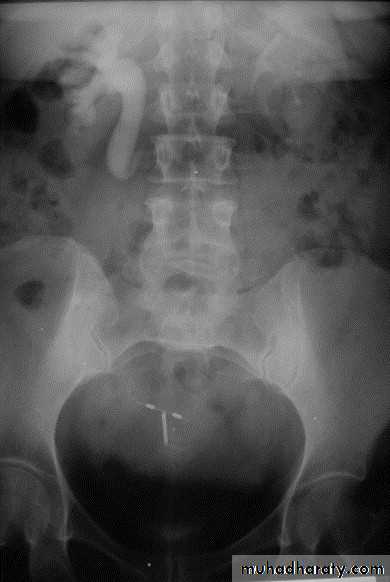

:*Ectopia vesica :-bladder located at low position with separartion of symphysis pubis.